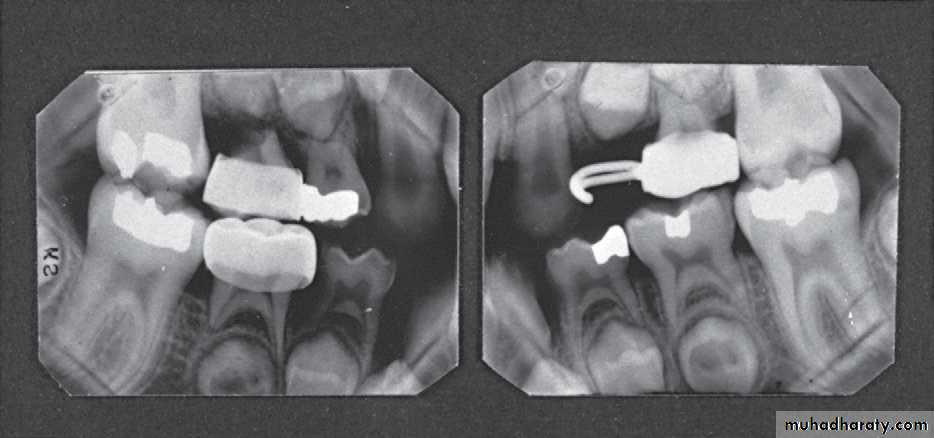

• Detect secondary cariesPosterior bite wing Radiograph

Record the width of spaces created by prematureloss of deciduous teeth

Indications of bite wing radiograph

(A) Interproximal caries detection;

(B) Evaluate the interdental bone